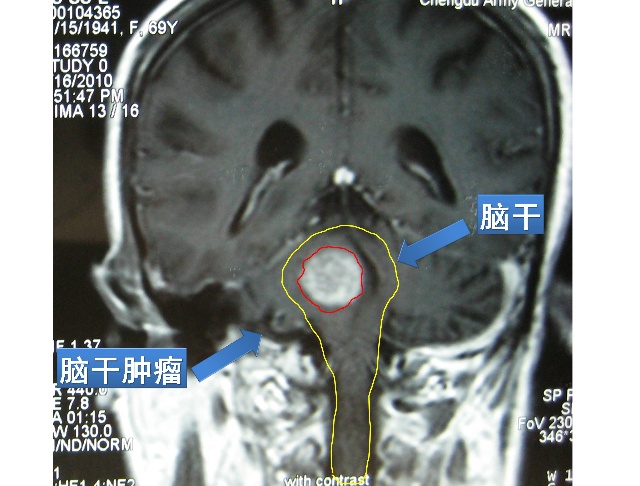

脑干是人体的生命中枢, 以往一直被认为是手术禁区。近年来的研究发现, 脑干有很大的可塑性,包括其形态及功能, 目前认为脑干的病变可以行外科手术治疗。脑干肿瘤在颅内相对少见, 依据发病年龄可分为儿童型和成年型, 美国脑肿瘤协会根据生长方式的不同将其分为弥漫型、局灶型、外生性、延脊髓型等类型。70%~80%的脑干肿瘤属于前两种类型, 不同类型的病例治疗方案不同, 有的限制生长, 有的最大限度的外科切除。延脊髓型脑干肿瘤发生率较低, 手术难度大, 临床表现、MRI、病理、治疗、康复及预后均有其特殊性。根据所在位置有两组不同的临床症状: 延髓征和颈髓征。延髓征包括: 恶心呕吐, 发育障碍, 言语障碍, 感觉迟钝, 上呼吸道感染, 睡眠呼吸暂停。颈髓征包括: 慢性颈痛, 伴无力和痉挛的颈髓病。MRI上肿瘤的实性部份在T1WI 中呈长T1 与稍长T1 的混杂信号影。肿瘤大多为良性的低级别的毛细胞型星形细胞瘤, 生长缓慢, 无浸润性生长的行为。少数为纤维型星形细胞瘤及血管网状细胞瘤。延脊髓是神经和传导束聚集的地方, 因而在此部位手术显露困难,致残率和病死率高,手术危险性大,术后并发症多, 预后不良。近年来,随着显微解剖、显微神经外科、神经放射学、神经麻醉学、超声吸引器和激光等技术和设备的迅速发展, 手术效果有明显改善。有人认为由于延髓颈髓交界区的胶质细胞瘤几乎都系低级别的, 很适合实施肿瘤的根治性手术, 且术后恢复较满意。显微手术一般采用保留自主呼吸的麻醉方式, 以利于术中密切监测呼吸变化, 不断提醒术者, 如切除过程中出现呼吸暂停或变慢, 可根据肿瘤的性质决定是否行姑息性治疗, 以免术后无自主呼吸而难以维持生存。传统手术方式一般采用枕后正中入路, 本组患者则采用小脑延髓裂入路。由于小脑延髓裂是位于小脑扁桃体和二腹叶下方与延髓之间向外行的一条自然裂隙, 经此裂隙,通过分离脉络膜和下髓帆, 到达第四脑室及延髓, 桥脑背侧, 显露下至延颈交界区, 上至中脑导水管下口的区域[8, 9]。与枕后正中入路相比较, 不切开小脑蚓部和小脑半球及避免过分牵拉小脑引起小脑功能障碍的并发症, 提高了患者的术后生存质量。同时将C1~3 椎板切除, 充分减压。手术操作时一定要轻柔,避免牵拉, 用微量双极电凝止血, 少许出血予以棉片压迫, 对于较大的血管止血, 应少许分离周围组织,夹闭, 轻轻提起血管, 再电凝。电凝应短暂多次, 反复冲洗, 防止过多热传导损伤周围脑组织。脑干听觉诱发电位(BAEP) 的波形改变非常灵敏, 术中尤为重要, 如若发现轻微的波形改变应暂停操作, 若很快恢复可继续进行手术。如波形改变后未恢复或恢复缓慢则停止手术, 而且提示预后不良。

脑干下端medullary-spinal brain stem tumors肿瘤发病率低,占脑干肿瘤的5%~10%, 由于其位置特殊、结构复杂, 神经外科医生一直将其视为手术禁区。近年来由于显微神经外科技术的飞速发展, 对此部位肿瘤多主张采取积极的手术治疗。一般临床表现吞咽呛咳, 声音嘶哑, 肌麻痹, 眼球震颤, 步态不稳, 强迫头位, 颈痛。影像学检查采用矢状位及轴位MRI检查, 可清晰地显示肿瘤的形态、轮廓、大小及与其周围结构的关系。手术microsurgery用小脑延髓裂入路, 即设计的皮肤切口上至枕外粗隆下至颈3, 咬开枕鳞、枕大孔和1~3 颈椎后弓, 颈延髓交界处打开硬脑膜释放脑脊液减压, “Y”字形剪开硬脑膜, 在手术显微镜下沿着小脑延髓裂( 位于小脑扁桃体和二腹叶下方与延髓之间向外行的一条自然裂隙) 通过分离脉络膜和下髓帆, 到达第四脑室及延髓, 桥脑背侧, 显露下至延颈交界区, 上至中脑导水管下口的区域。通过此操作多数肿瘤可得到充分的显露。胶质肿瘤有囊变则抽出囊液, 侧方切开,瘤内吸除肿瘤, 逐渐向外至正常组织。血管网织细胞瘤先用极小功率电凝进入肿瘤的供血动脉和表面血管, 小心分离瘤体, 一边止血, 一边游离肿瘤, 直到肿瘤主体与脑干脱离, 再予以摘除, 注意保护小脑下前动脉及小脑下后动脉的主干。同时将C1~3 椎板切除。肿瘤切除后严密缝合硬脑膜。